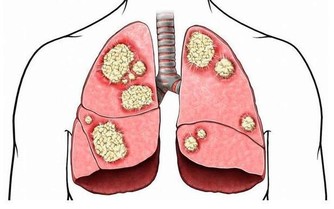

3、腦梗塞

有腦梗賽病史的患者多有頭暈的臨床表現,頭暈表現為持續性,是腦血管梗阻後,相應區域內腦組織供血不足導致的。